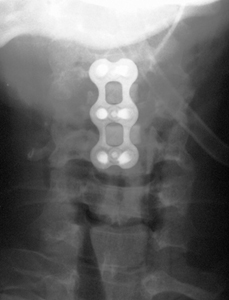

ACDF X-Ray

3. Stabilization of the fusion with a metal plate and screws.

The surgery is performed through a small skin incision in the front of the neck. The esophagus and windpipe are pushed to one side, allowing direct access to the anterior cervical spine. With the aid of a high-powered microscope, the herniated disc and bone spurs can be removed with microsurgical instruments to relieve pressure on the nerves and spinal cord. The fusion is obtained by placing bone graft within the disk space. This bone graft maintains the disc space height and allows bone cells to grow from one vertebra to another. A metal plate and screws are placed over the graft and vertebra to stabilize the spine during the fusion (healing) process. The skin is closed with dissolvable sutures and sterile superglue.